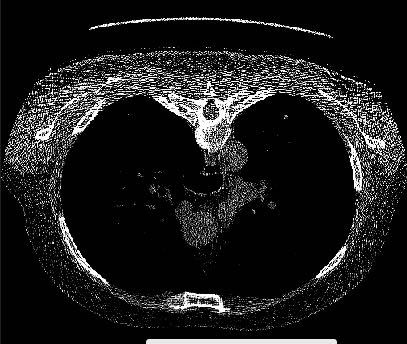

求大神解答,为啥我从vtk读取一个dicom图片,显示的如图二,但真实的是图一,这是为啥

1. 坐标问题,把其中一个旋转180度看看

2. 窗宽窗位问题,具体自行百度